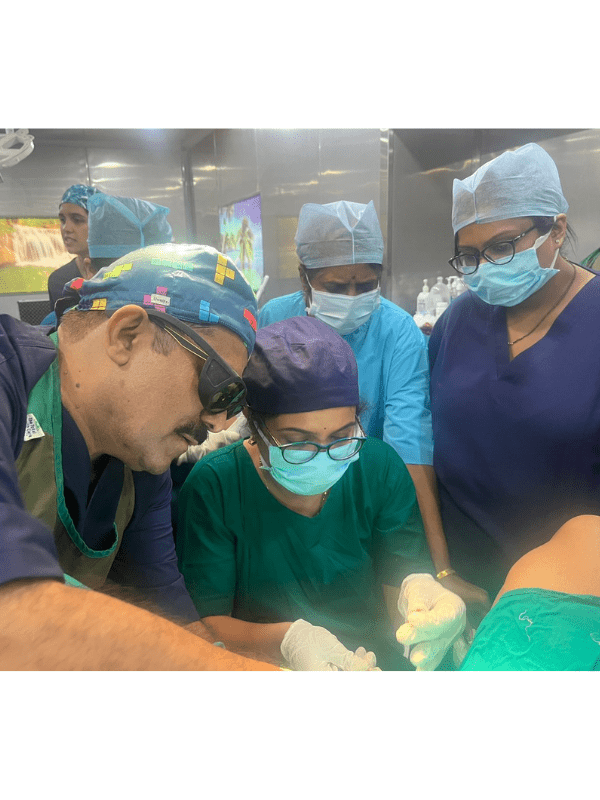

Operative

Our skilled neurosurgeon performs transformative operative procedures, harnessing the power of cutting-edge techniques to improve and restore neurological health. Experience the precision and expertise of our neurosurgeon as they prioritize your well-being and deliver exceptional surgical care for optimal health outcomes.

Minimal Invasive Brain Surgery

Our skilled neurosurgeon performs state-of-the-art minimal invasive brain surgeries, employing advanced techniques to minimize trauma, accelerate recovery, and optimize overall neurological health. Experience the benefits of precise and innovative surgical interventions tailored to your specific condition, enhancing your well-being and quality of life.